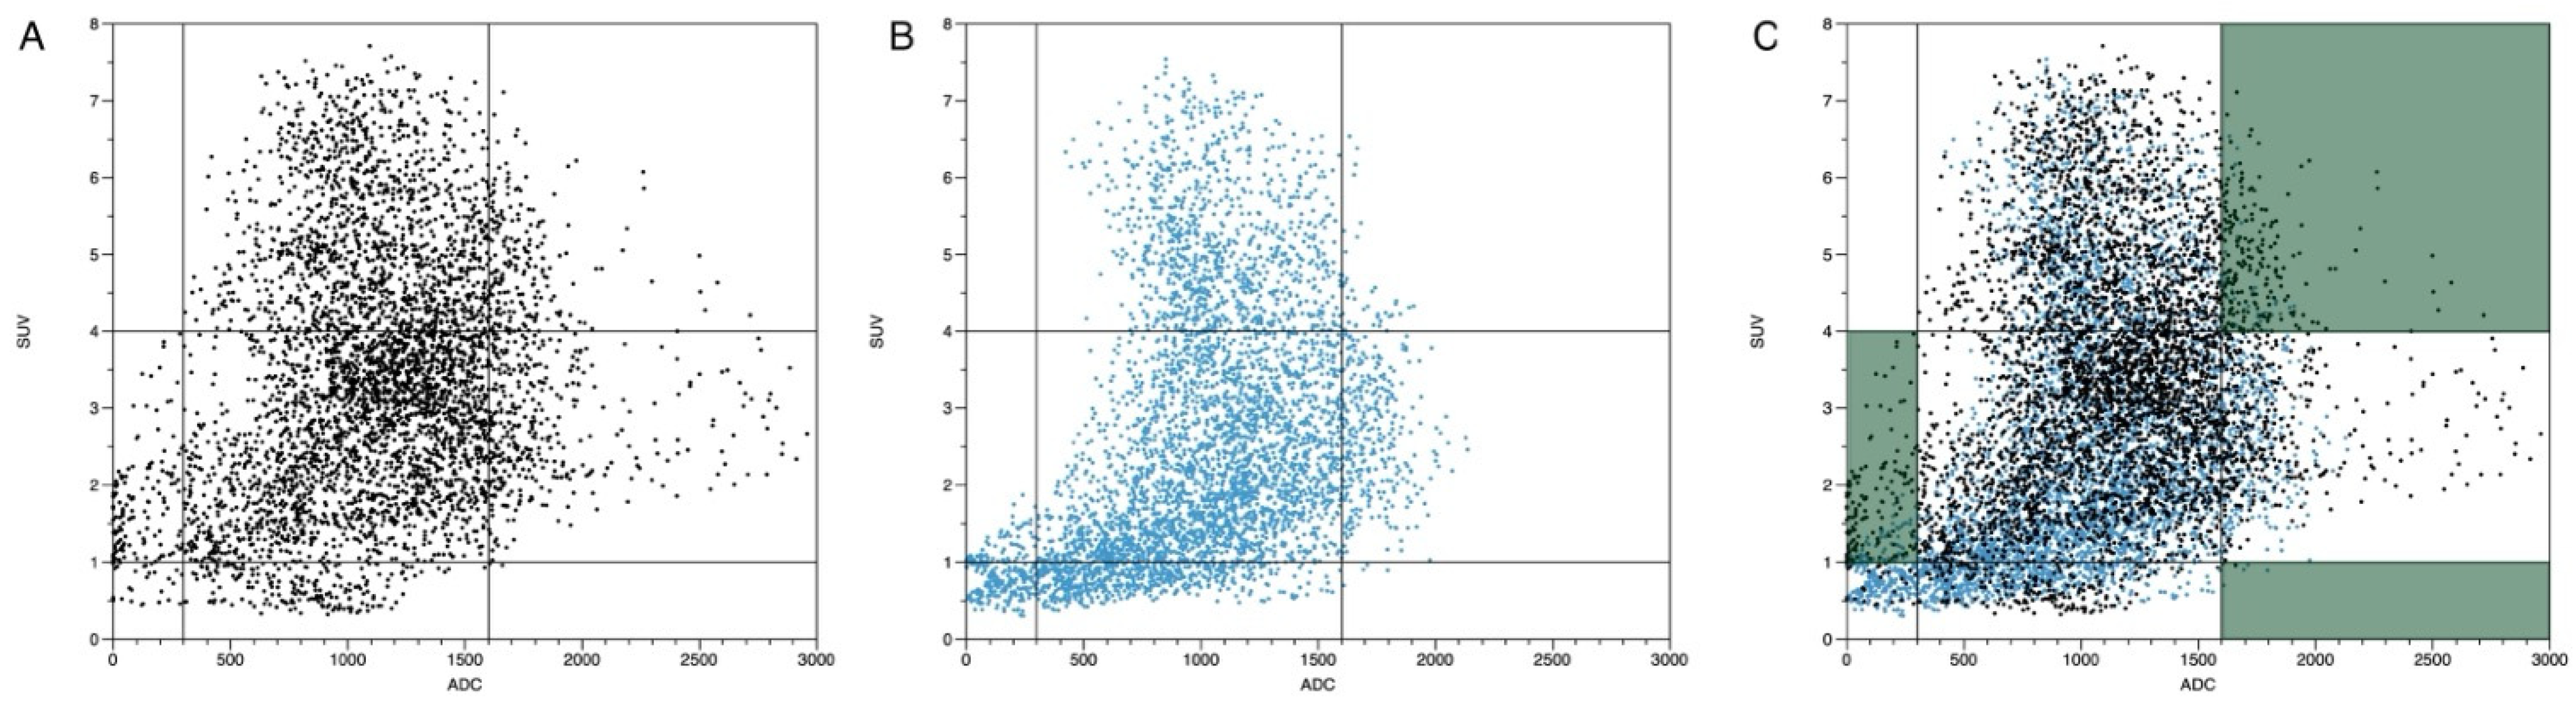

- -

- ADC < 300 mm2/s in combination with an SUVbw > 4.

- -

- ADC > 1600 mm2/s in combination with an SUVbw > 4.

- -

- ADC > 300 mm2/s and < 1600 mm2/s in combination with an SUVbw < 1.

3.5. Plausibility of DWI and PET Images